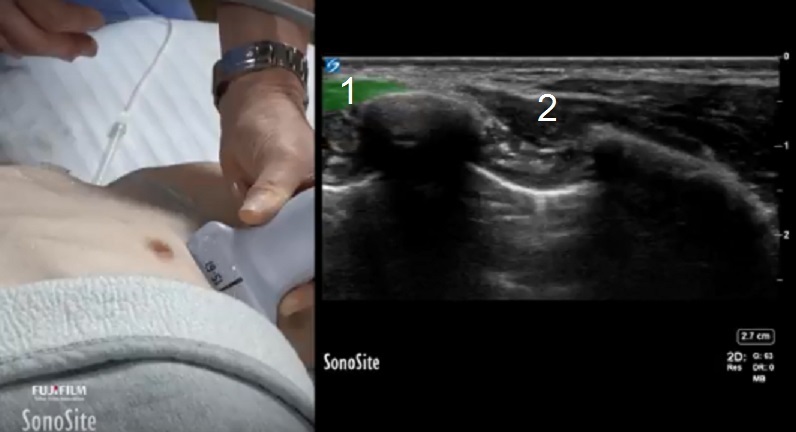

広背筋前鋸筋グラフィックとイメージ

広背筋

前鋸筋